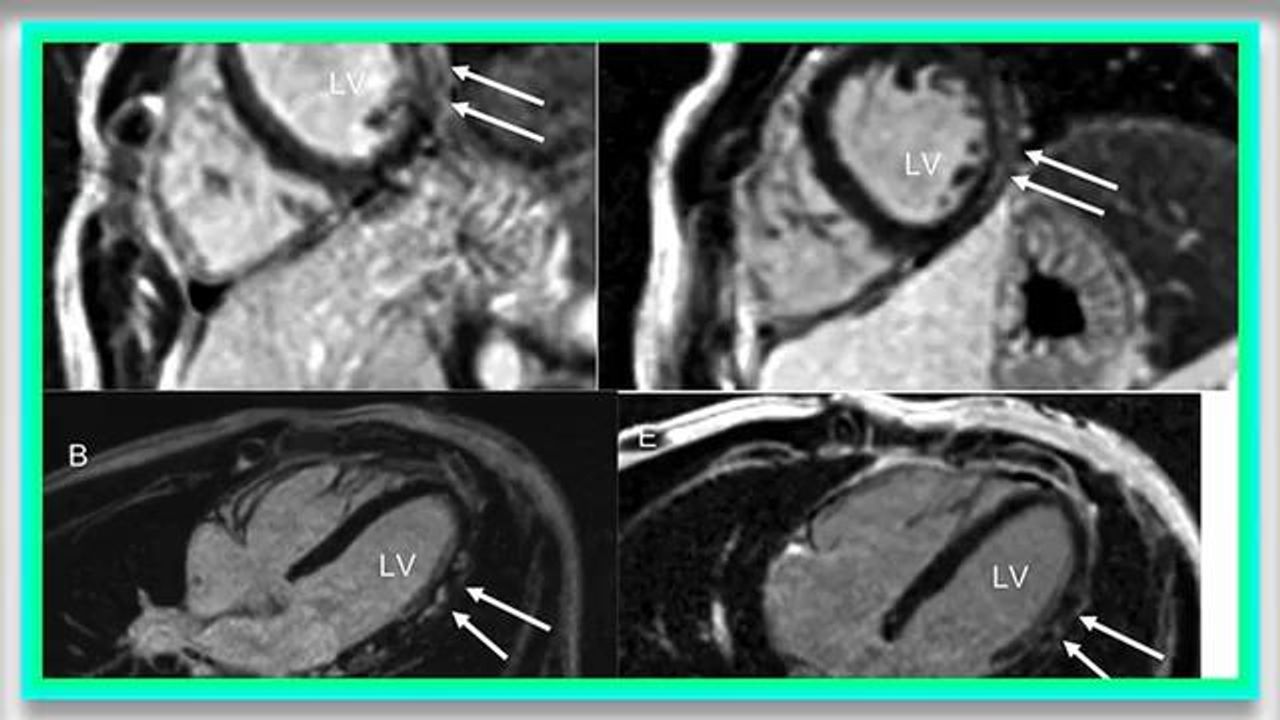

Myopericarditis, has emerged as an important adverse event following COVID-19 mRNA vaccination, particularly in adolescents [[1]]. Patients typically exhibit chest pain and an elevated serum troponin level in the days following the COVID-19 mRNA vaccine. They usually are hemodynamically stable, and symptoms and cardiac biomarkers normalize within a few days [[2]]. cardiac magnetic resonance studies, when performed early, frequently demonstrate abnormalities such as edema and late gadolinium enhancement (LGE), meeting Lake Louise Criteria for diagnosing myocarditis noninvasively [[2],[3]]. In classical myocarditis LGE can be predictive of a poor outcome [[5]]. Little is known about the prognostic value or expected evolution of these CMR abnormalities associated with post-COVID-19 mRNA vaccine myopericarditis. In this case series we report the evolution of CMR imaging compared with initial, acute phase, CMR in our cohort of patients with myopericarditis post COVID-19 mRNA vaccine.